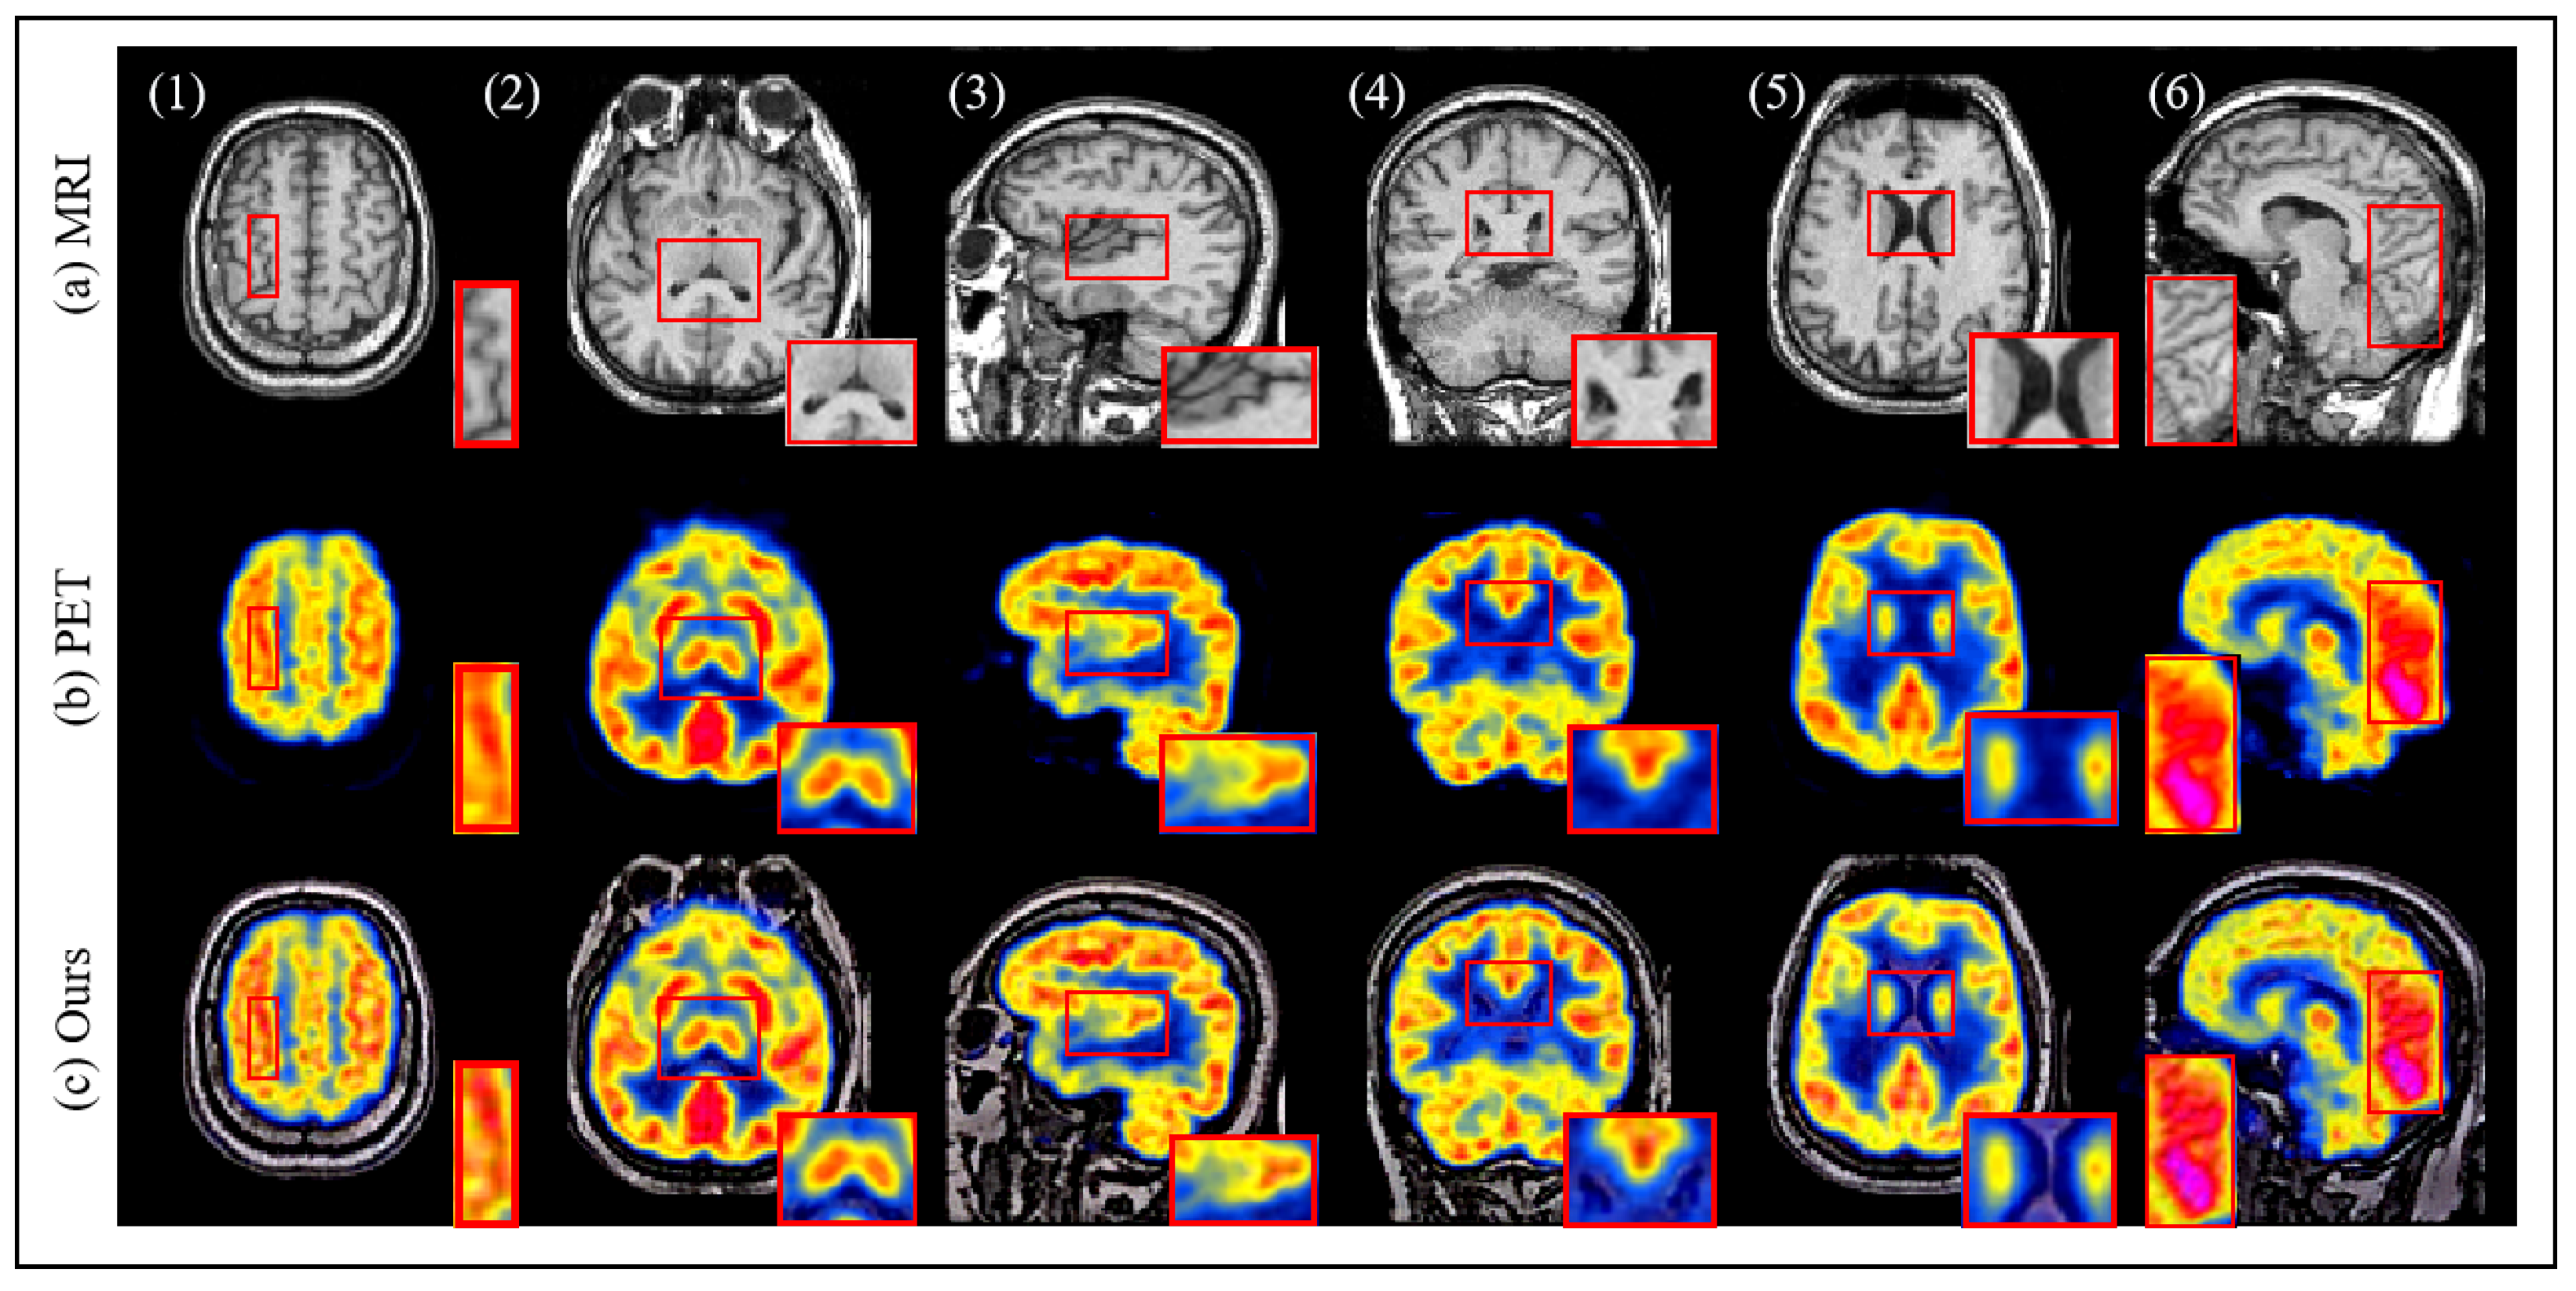

4.3. Results and Discussion